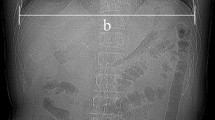

where A is the maximum aortic enhancement, t is time, τ is the decay constant, b is the power, and C is the initial pre-contrast aortic enhancement. The first and second derivatives of the gamma fit were also computed. The ideal time-to-peak (Tg) in seconds between the ideal base and ideal peak of the aortic enhancement was calculated as the time difference between the maximum of the second derivative of the gamma variate fit and the peak of the actual gamma variate fit. The results were then compared to one half the contrast injection time using regression analysis. Example gamma fits are shown in Fig. 2. The gamma variate fit results were also analyzed to determine if there were pair-wise differences in heart rate, time-to-peak, and peak enhancement between rest and stress conditions. Additionally, in the five animals with significant stenoses, the gamma variate fit results were further analyzed to determine if there were pair-wise differences in time-to-peak between rest or stress acquisitions without stenosis as compared to stress acquisitions with significant stenosis.

Automatic gamma variate fitting of the aortic enhancement in two swine. a The gamma fit (black), first derivative (blue), second derivative (red), and time-to-peak (Tg) are displayed for a 45-kg animal with a 9-s contrast injection. b The gamma fit (black), first derivative (blue), second derivative (red), and time-to-peak (Tg) are also displayed for a 95-kg animal with a 19-s contrast injection